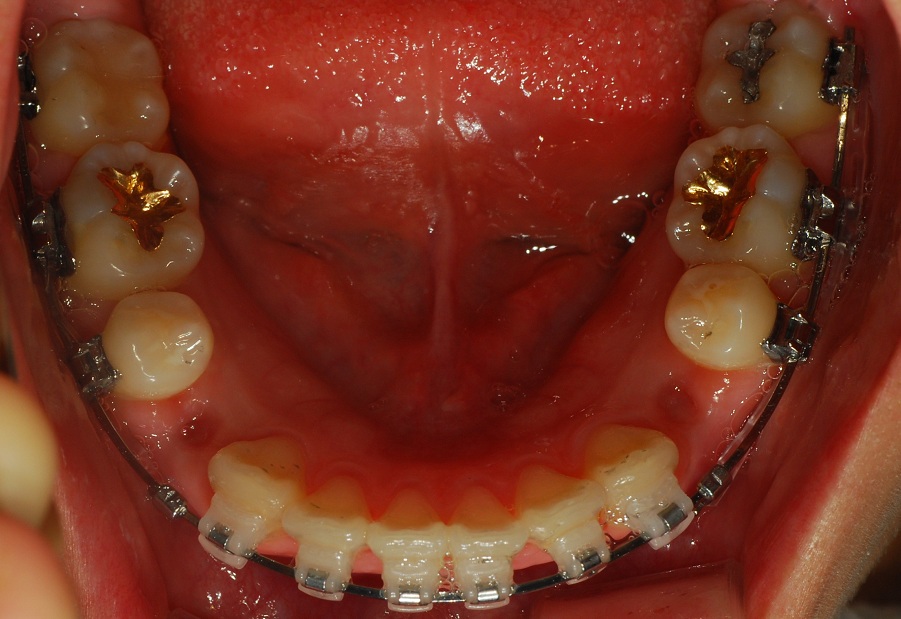

상악 치아 모습입니다. 발치한 부분이 잘 아물고 있네요~

하악 치아 모습입니다.